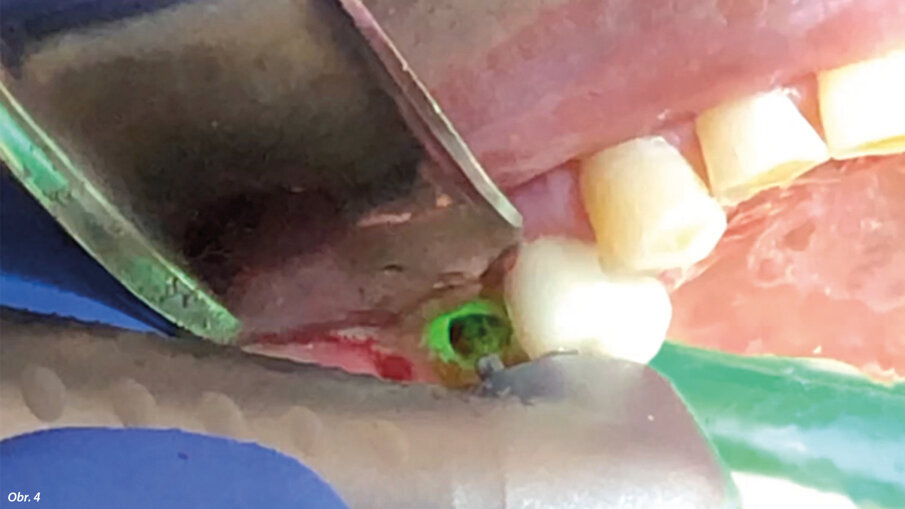

67letý pacient, nekuřák, bez jakýchkoli systémových onemocnění, byl vyšetřen pomocí CBCT (PaX-i3D Smart, Vatech) za účelem vyhodnocení operované oblasti, objemu kosti a hustoty kosti v bezzubé oblasti zubu 15 (obr. 1). Před chirurgickým zákrokem obdržel pacient veškeré informace týkající se ošetření a prostřednictvím individuálního informovaného souhlasu byl informován o možných alternativách ošetření. Osa zavedeného implantátu byla naplánována s ohledem na dosažení nejlepšího funkčního výsledku náhrady. Pro intraorální oporu Er:YAG násadce ve správné poloze odpovídající ose zavádění implantátu byl vytvořen individuální držák z dentální pryskyřice. Byla aplikována lokální anestezie ve formě artikainu (1 : 100 000). Pomocí Nd:YAG laseru (vlnová délka 1 064 nm; vlákno o průměru 200 μm; MSP: 3 W, 70 Hz; LightWalker AT, Fotona) byl na palatinální paramediální linii proveden mukoperiostální řez a současně s ním i dva meziální a distální uvolňující řezy nezasahující papilu (obr. 2). Přístupový lalok pak byl odklopen Prichardovým elevátorem (obr. 3).

Před zákrokem byl pořízen CBCT sken.